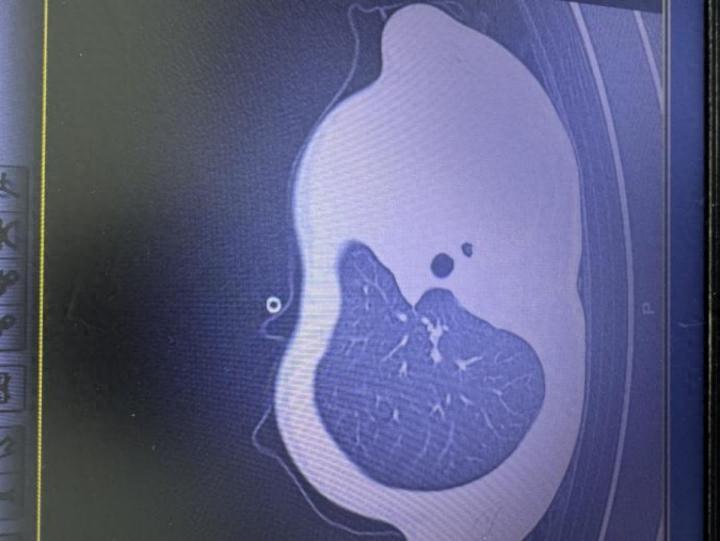

急诊查验浪漫让医护东说念主员须臾垂死:验血流露炎症场所大幅高潮,胸片更发现左侧肺叶险些“不使命了,影像学中变成大片白色,即往往所说的“白肺”,意味着肺功能严重受损,孩子依然缺氧,随时有窒息危急。

影像流露肺白了一半